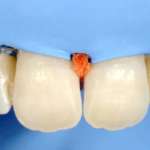

Le fondamenta del restauro estetico: i perni in fibra di vetro

Con il passare degli anni i trattamenti post-endodontici hanno subito diverse evoluzioni che hanno portato oggi all’utilizzo di tecniche più conservative. In questo caso clinico viene descritta una tecnica di restauro post-endodontico in un elemento 2.1 molto compromesso. La parte demineralizzata è stata rimossa e sostituita con restauri diretti con tecnica adesiva chairside e l’aggiunta di un perno in fibra di vetro, a sostegno della ricostruzione, per evitare il rischio di fratture radicolari.